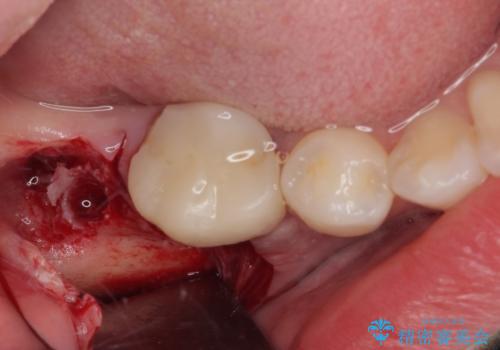

埋伏している右下第二大臼歯は、牽引して咬合に参加させることで計画しましたが、癒着などにより移動困難な場合には、抜歯の上インプラント補綴治療を行うこととしました。

右下の埋伏歯はやはり癒着しており、抜歯の後にインプラントを埋入することとなりました。